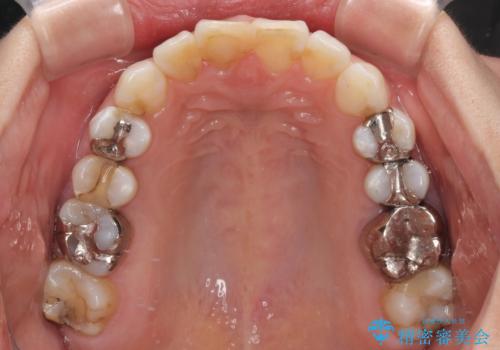

- 前歯のデコボコを治したいとのことで来院された患者様です。

上下顎ともに歯列全体の後方移動とIPR(歯と歯の間を削る)によってデコボコが解消するように設計し、インビザラインにより治療を行うこととしました。